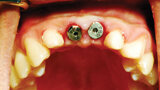

Fig. 8: Picasso Lite+ diode laser removing soft tissue to uncover the implants’ cover screws. (Photo provided by Dr. Gregori M. Kurtzman)

Fig. 9: Uncovery of the implants and healing screws exposed. (Photo provided by Dr. Gregori M. Kurtzman)

Fig. 10: Healing abutments placed into the implants. (Photo provided by Dr. Gregori M. Kurtzman)